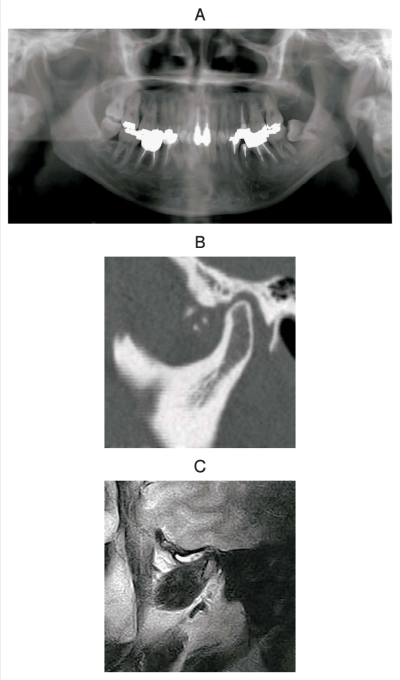

56歳の男性。開口障害を主訴として来院した。3か月前から症状があるという。最大開口量は 28 mmで、開口時に左側顎関節に疼痛を認める。初診時のエックス線画像、CT及びMRIを別に示す。

最も疑われるのはどれか。1つ選べ。